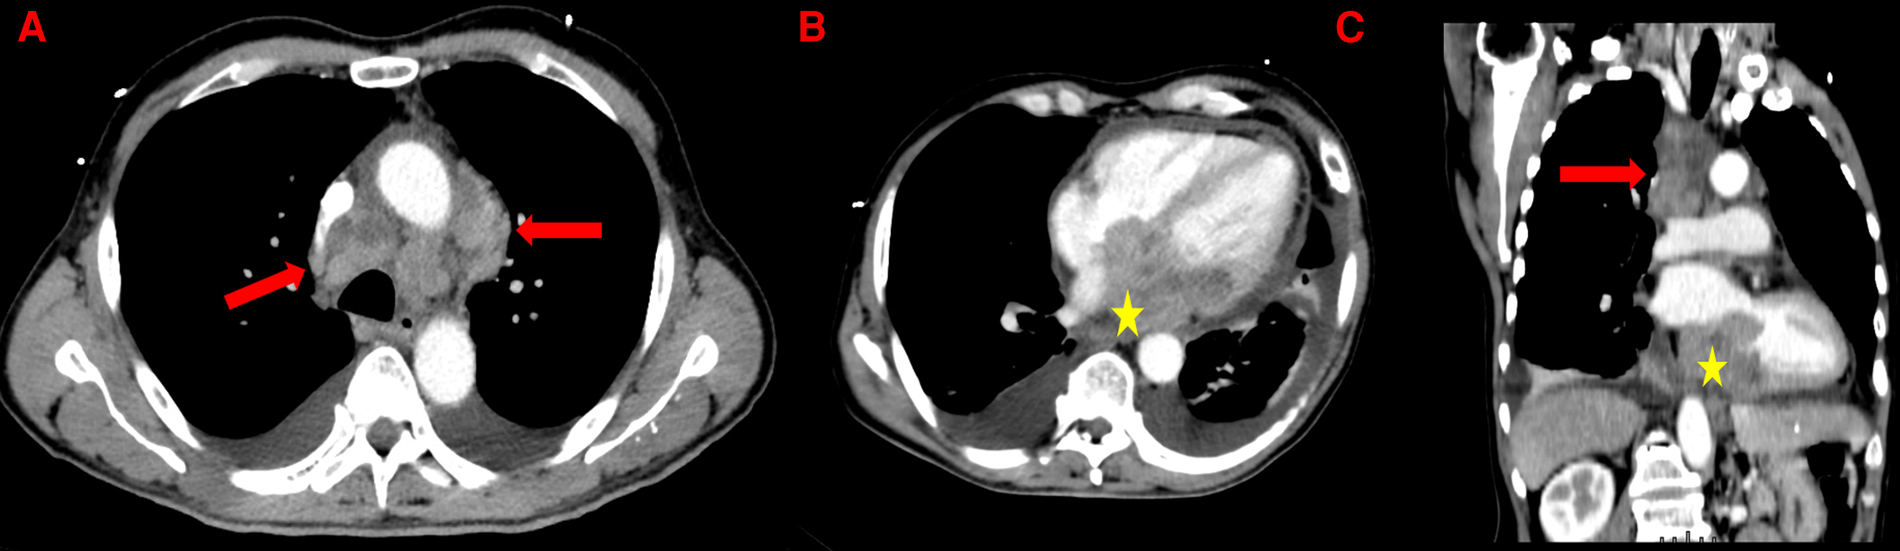

Figure 1

Thoracic CT-scan showing mediastinal lymphadenopathies (red arrows) and the left atrial mass (yellow stars) in axial view (A and B) and in coronal view (C). Presence of a bilateral pleural effusion and a thickened pericardium (B).

In March 2022, a 63-year-old man without notable past medical history presented with rapidly progressive exertional dyspnea associated with night sweats. The electrocardiogram revealed complete atrioventricular block (AVB) with a heart rate of 40 beats per minutes and narrow QRS complexes. Lab tests showed anemia with hemoglobin at 9 g/dl, normal renal function and a biological inflammatory syndrome with CRP at 181 mg/L (normal upper limit: 4 mg/L) and the patient was transferred to the intensive care unit with Isoprenaline infusion. The initial workup included a bedside transthoracic echocardiography, which revealed a heterogeneous left atrial mass, measured at 50 × 60 mm, infiltrating the inter-atrial septum with an extension into the right atrium measured at 43 × 26 mm. This mass seemed to be implanted in the lateral wall of the left atrium and prolapsed into the mitral valve causing moderate mitral regurgitation and significant mitral stenosis with a mean gradient ranging from 7 to 14 mmHg. Then, a thoracic, abdominal and pelvic CT scan was performed and showed the cardiac mass associated with a mild pericardial effusion, hilar and mediastinal lymphadenopathy and bilateral moderate pleural effusion (Figure 1). The workup was completed by a cardiac magnetic resonance imaging (CMR) study to better characterize the mass. CMR confirmed the presence of a bulky mass with a “cauliflower” appearance, extending throughout the entire left atrium, infiltrating the interatrial septum and the right atrium as well as the basal inferior and inferolateral walls of the left ventricle (Figure 2A). This mass appeared isointense on black blood spin echo T1-weighted imaging, slightly hyperintense on fat saturated T2-weighted imaging with a heterogeneous enhancement on late gadolinium enhancement (LGE) sequences (Figures 2B,C), suggestive of a malignant tumor. In order to distinguish between cardiac lymphoma or sarcoma, for which initial treatments are diametrically opposed (i.e., urgent chemotherapy vs. surgical resection) (1), a myocardial biopsy guided by transesophageal echocardiography was performed. Four endomyocardial fragments were collected from the right atrial side of the interatrial septum via a femoral venous access. Given the persistence of complete AVB at day 7, a VVI single lead transvenous pacemaker was implanted. Prompt pathological analysis revealed the presence of a diffuse large B-cell lymphoma classified as germinal center B cell type (CD10+, BCL6+, MUM1+), with a double expression of MYC/BCL2 (Figure 3). Urgent treatment was initiated as soon as the pathology results were obtained, 10 days after the biopsy, with corticosteroids (1 mg/kg) associated with chemotherapy including rituximab, cyclophosphamide, doxorubicin, vincristine, and prednisone (R-CHOP). Six cycles of R-CHOP were completed within 6 months, allowing a clear improvement of the dyspnea and of the overall condition. CT-scan after the fourth cycle of R-CHOP showed complete remission of the lymphoma (2). After setting the MR conditional pacemaker to DOO mode, follow-up CMR revealed complete disappearance of the cardiac mass (Figures 2D–F). Because the patient was in spontaneous sinus rhythm at the last visit and the stimulation rate dropped from 100% to 26% after the third R-CHOP cycle, an evaluation by the cardiac electrophysiologist was scheduled 3 months later to assess the percentage of RV pacing for possible pacemaker removal. Written informed consent was obtained from the patient for the publication of any potentially identifiable images or data included in this article.